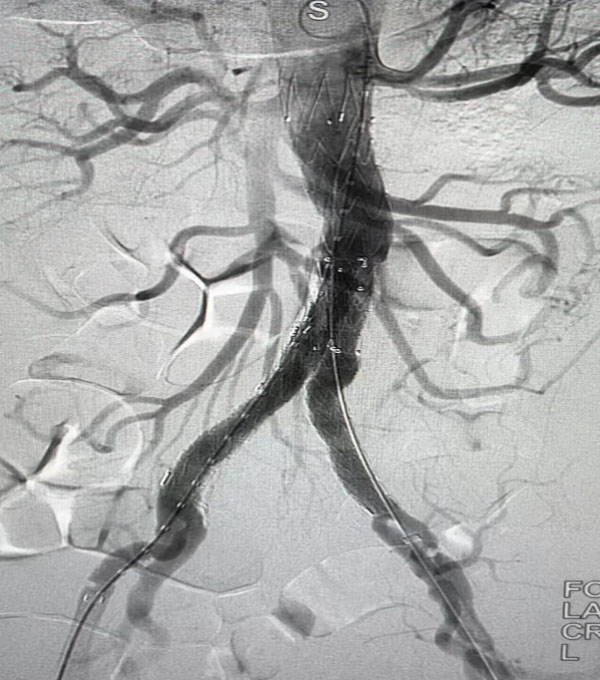

同期,另一台“升主动脉置换+全主动脉弓置换+胸主动脉覆膜支架腔内隔绝术”正在开展,该病例为一名A型主动脉夹层患者。在主动脉弓及分支成功游离且心脏停跳后,心外科负责人赵永波“转场”为患者完成了血管置换,心脏复跳成功,止血彻底。随后,谈凌凌主治医师、侯五辉主治医师为患者进行胸主动脉腔内修复。下午2点左右,两台手术成功结束。通过现场视频直播,在手术同时,手术人员与大会现场的专家们就影像评估、手术策略、手术器械的选择及操作技巧等多个环节进行了互动讨论,学术气氛热烈,大会主席及与会代表给予我院高度评价。紧接着,手术团队又为一名79岁腹主动脉瘤患者进行了腹主动脉腔内修复手术,效果良好,同样受到与会专家的好评。

腹主动脉腔内隔绝